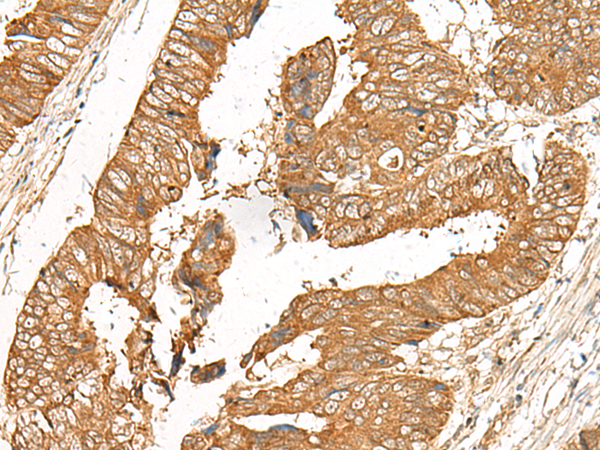

ELISA, IHC |

IHC positive control: |

Human cervical cancer and Human colorectal cancer |

IHC Recommend dilution: |

50-300 |